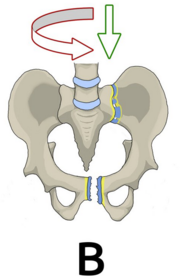

Typ B Beckenringverletzung mit rotatorischem Stabilitätsverlust mit inkompletter Durchtrennung des hinteren Beckenrings und erhaltener vertikaler Stabilität -> Partiell instabil. Beeinträchtigte Stabilität im hinteren Beckenring, Rotationsstabilität einer Beckenseite.

Was bedeutet rotationsinstabil? Bei Riss der Symphyse besteht Rotationsinstabilität, das heißt, dass bei horizontaler Krafteinwirkung die Beckenhälften unter Dehnung des Iliosakralgelenks auseinanderweichen.

Was sind Beispiele für Typ B? Nenne drei: Typ B1: Symphysensprengung ("open-book") Typ B2: Laterale Kompressionsverletzung Typ B3: Beidseitige B-Verletzung

Wie sehen Frakturen Typ A - C aus?